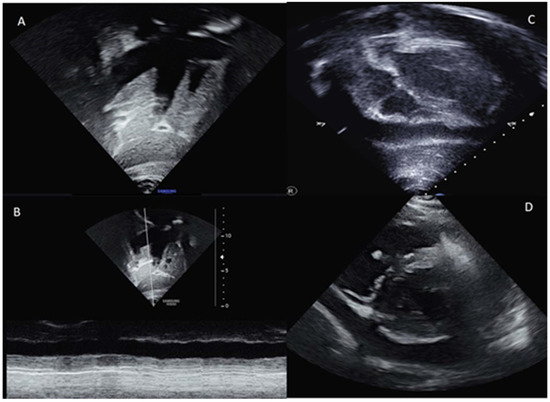

2. Case Presentation